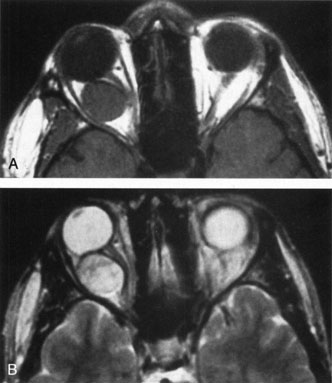

If NFM is suspected, MRI should be ordered of the orbits and brain to exclude noncontiguous intracranial anomalies.93 Magnetic resonance imaging demonstrates the dilated cystic spaces with either a hypointense (lymphatic cyst) or hyperintense (hemorrhagic cyst) signal on T1-weighted images, and a hyperintense signal on T2-weighted images (Fig. 10, A&B).94Layering may be seen within the cysts if there has been a recent hemorrhage leaving unresorbed blood. The CT scans of patients with a deep NFM show low-density, poorly defined masses behind the orbital septum in the extraconal and intraconal spaces, which may indent the globe.3 Calcification within the mass (Fig. 11) and inhomogeneous enhancement of the rim and focal areas within the lesion may be seen that corresponds to abnormal endothelially lined channels.3 Enlargement of the bony orbit can occur, particularly with combined lesions.3,89 If the diagnosis is still unclear, ultrasonography can be performed. A cystic orbital mass is seen on B-scan. A-scan shows features of a solid, cellular tumor: low reflectivity, regular homogeneous internal structure, and marked sound attenuation through the mass.3,89 Standard pulsed Doppler ultrasound confirms no intrinsic flow within the lesions.

Fig. 10. A and B. No flow malformation of the orbit. Sagittal magnetic resonance imaging showing dilated cystic spaces hypointense to muscle on T1-weighted images (A) and hyperintense to muscle on T2-weighted images (B).